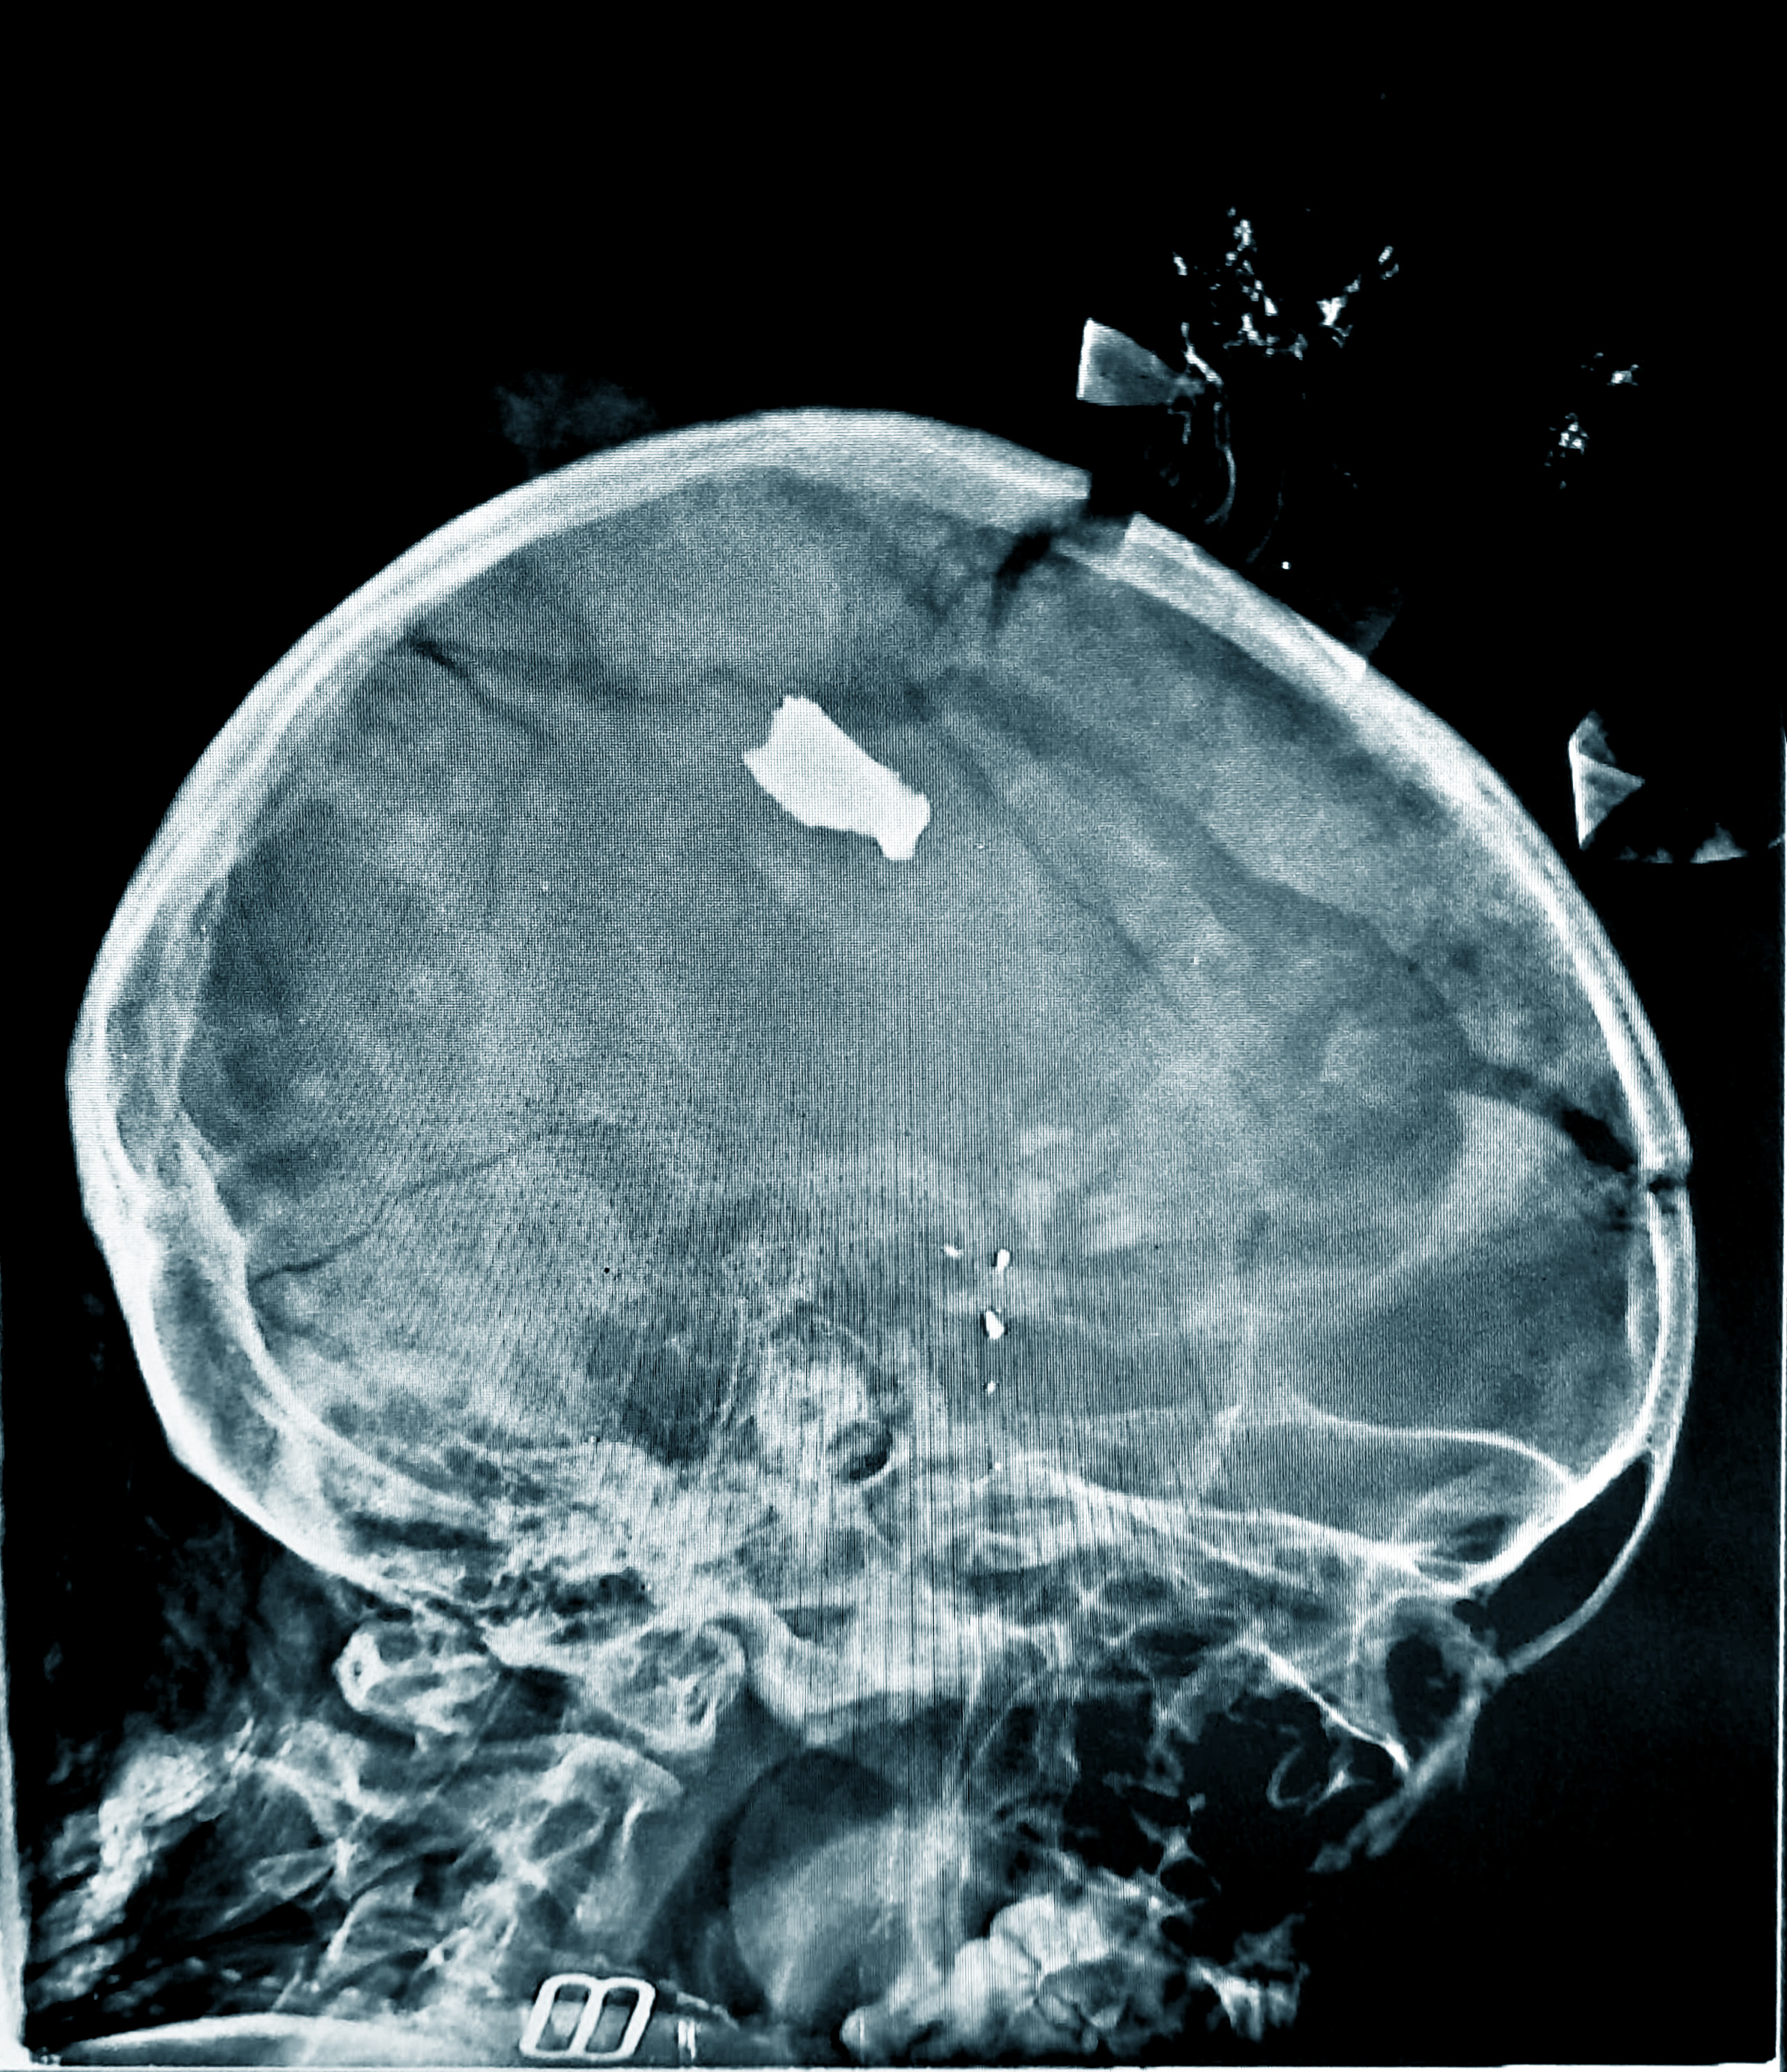

I slutet av oktober kom fler än 30 krigsskadade patienter till Bashair Teaching Hospital på en dag efter en explosion på en marknad mindre än en kilometer bort. Tolv av de som fördes till akuten var barn under 15 år. Många hade brännskador och traumaskador. En flicka på snart två år hade splitter djupt inne i huvudet. När teamet försiktigt lade henne på röntgenbordet ramlade en del av det lilla huvudets ömtåliga skallben ner på bordet.

– Sådana fall är vanliga, säger läkaren Moeen*. Tack och lov överlevde den lilla flickan. Andra har inte samma tur.